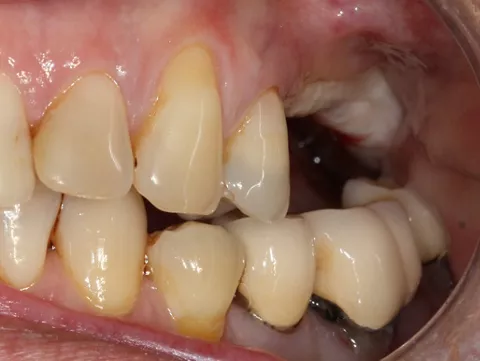

A 60-year-old female patient presented at our office. She was in good health and a non-smoker, and had healthy periodontal tissue and good oral hygiene. Teeth 25, 26, and 27 had been missing for several years, and there was insufficient bone to place implants. However, quadrant four had been the priority, with 3 Axiom® REG implants being placed there in 2019. An inspection of quadrant three revealed significant damage to 36 and misalignment of 37.

3a-b & 4a-b. Preoperative situation.

Free-end saddle. Periodontal tissue appeared healthy. Plenty of keratinized tissue. Notice the more extensive vestibular bone loss around 25.